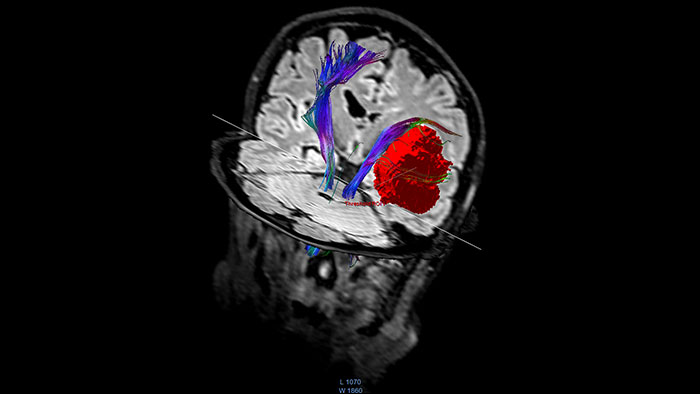

FiberTrak

MR FiberTrak

Visualize white matter connectivity in the brain

Provides visualization and quantification of white matter structure in the brain and spinal tracts using task guidance for generating common or user-defined tracts.

FiberTrak thumbnail

Benefits

• The guidance panel suggests which regions of interest and plane are common for identification of certain tracts such as the corticospinal tract.

• The results can be overlaid with other data like fMRI or anatomical series.

• Allows evaluation of fiber tracts around tumors and lesions in combination with functional areas.

• Supports DICOM-based output with merged anatomical tractography information through the Multi Modality Viewer.